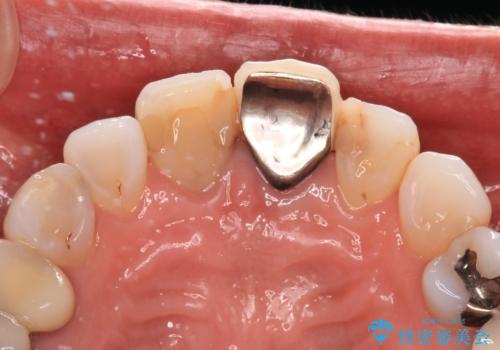

- 変色した保険の前歯のクラウンを交換したいとのことで来院された患者様です。

中心左側の歯はクラウンが装着されており、右側は神経組織が除去されて多少変色している状態でした。

右側の歯も将来的にもっと変色する可能性があるため、前歯2本をオールセラミッククラウンにて補綴治療を行うこととしました。